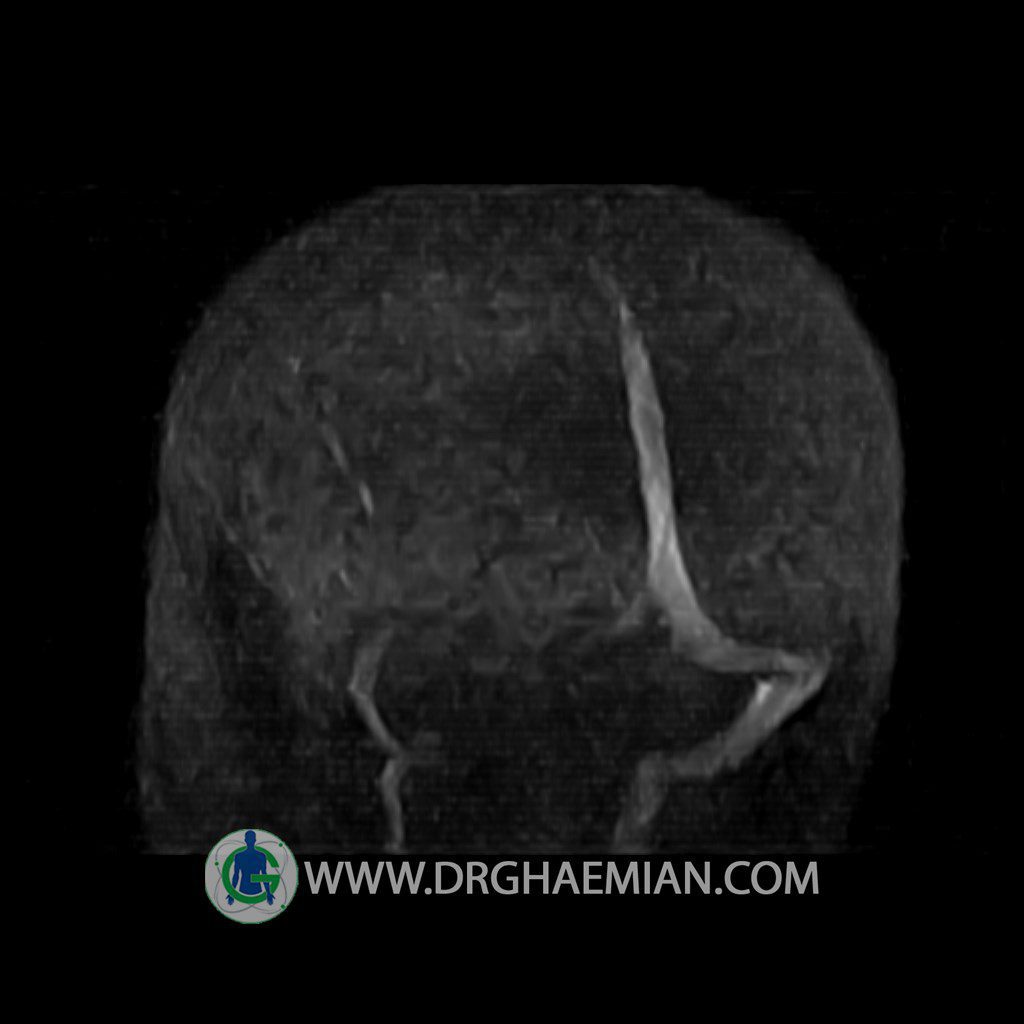

ام آر وی یک روش تصویربرداری دقیق و غیر تهاجمی است که برای معاینه ورید های بدن و ارزیابی سلامت رگ ها استفاده می شود. ورید ها خون را از اعضای بدن به قلب باز می گرداند تا دوباره اکسیژن و مواد مغذی به خون داده شود. ام آر وی جریان خون را ارزیابی و موارد غیرعادی مضر مانند لخته های خونی را شناسایی می کند. در این کیس ترومبوز دیواری مغز در سینوس عرضی راست و ترمبوز جزئی در سینوس عرضی چپ دیده می شود.

Technique: TOF ( time of flight ).

– Narrowing of left transverse sinus with filling defect & inthimal irregularity

suggestive for partial thrombosis

– Inthimal irregularity in anterior wall of right transverse sinus suggestive for mural thrombosis

are seen